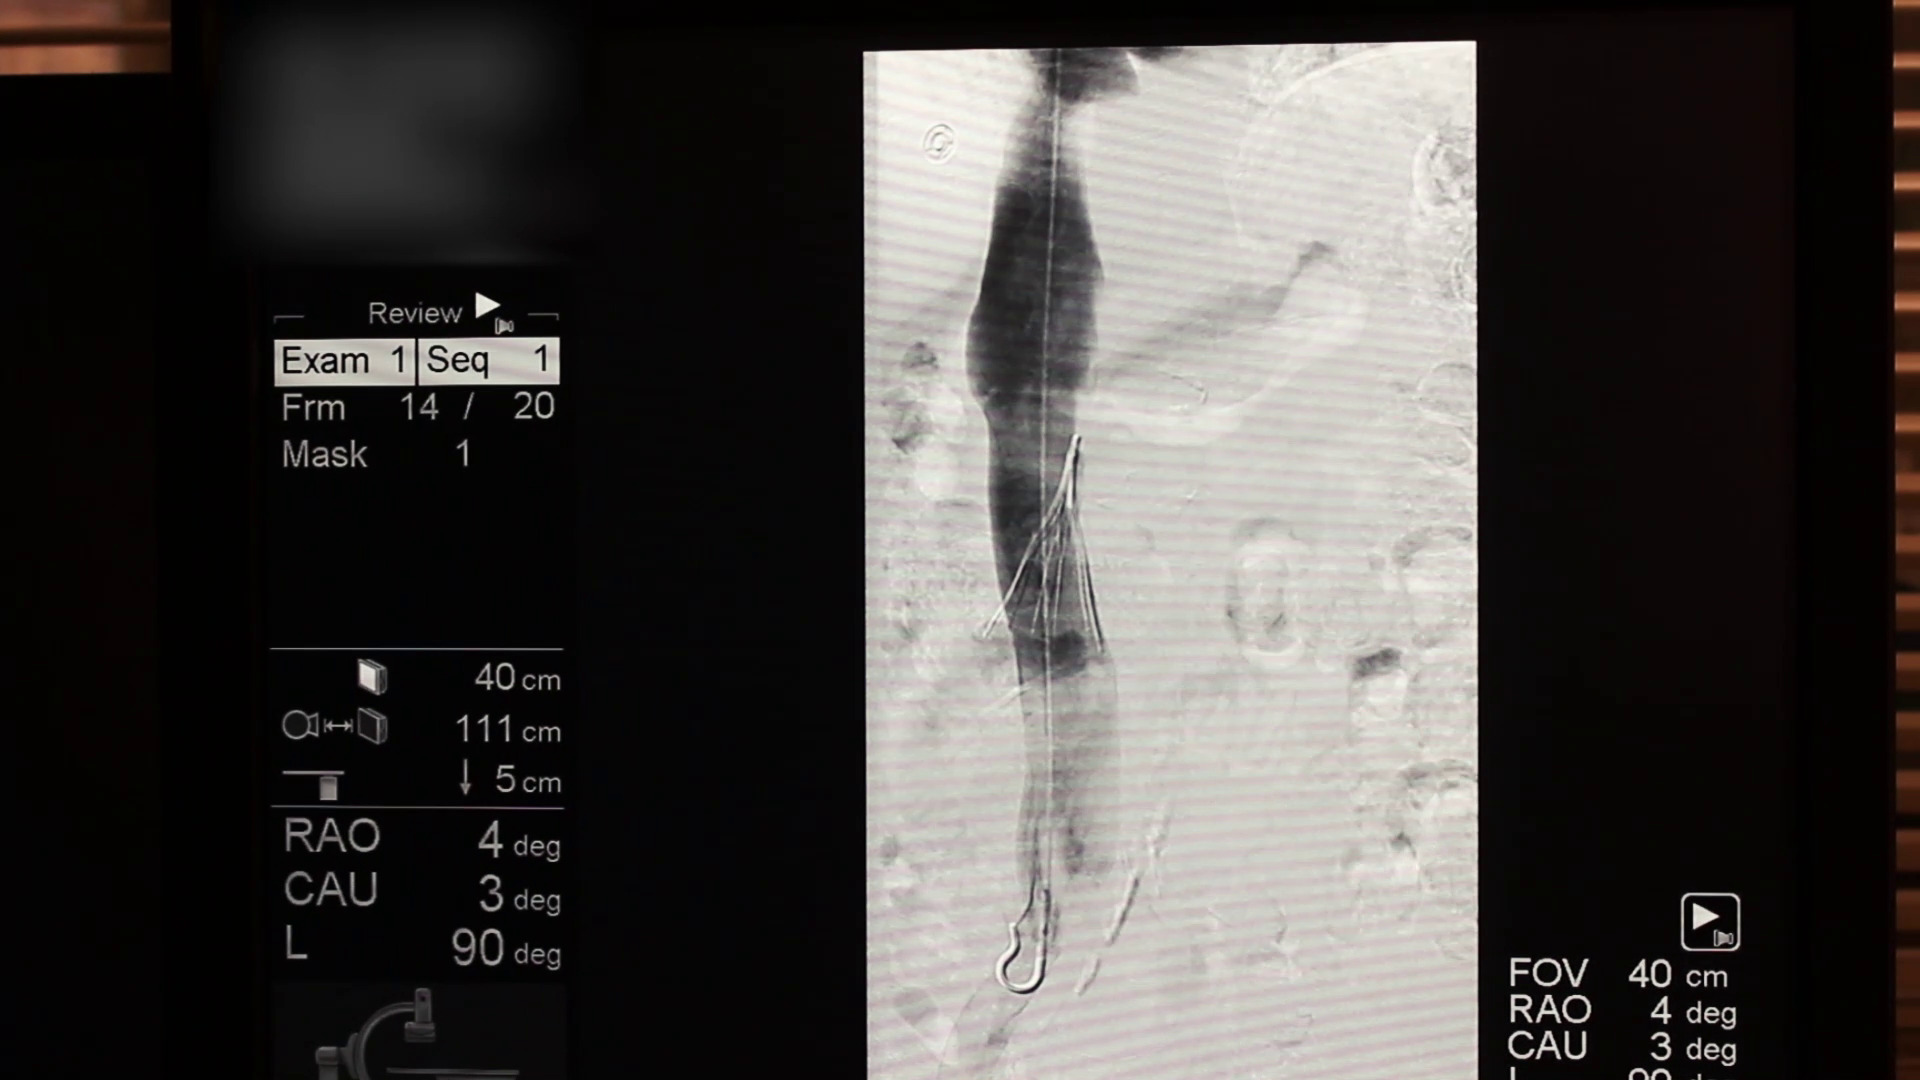

Watch the Full VideoIntroduction: Cricopharyngeal dysfunction (CPD) is a spectrum disorder encompassing multiple entities that ultimately result in dysphagia as a result of disruption of the normal anatomy or physiology of upper esophageal sphincter. It is a known and well described cause of dysphagia in adults, however, it’s role in pediatric dysphagia is less clear and limited to mostly small case series.1 Despite it’s relatively low prevalence, the complex pediatric otolaryngologist must be aware of this entity and it’s management. We discuss a complex case of CPD with an associated cricopharyngeal bar and pharyngeal diverticulum, as well as our successful endoscopic surgical approach highlighting the principles of CPD management in children. Case Presentation: We present a 21 month of female with a history of DiGeorge Syndrome and oropharyngeal dysphagia. Despite appropriate conservative measures including feeding therapy and diet thickening modification, as well as attempted Botox injection, the patient continued to demonstrate dysphagia. It was also noted on her swallow study that she had a posteriorly based pharyngeal diverticulum that potentially served as an aspiration reservoir. The decision was made to proceed with endoscopic cricopharyngeal division and diverticulum marsupialization. Technique: With the patient intubated, a Lindholm laryngoscope was placed posteriorly into the hypopharynx, elevating the larynx and allowing visualization of the upper esophageal sphincter and isolation of the cricopharyngeal bar. A non- contact CO2 laser fiber at 2W continuous spray was then used to divide the cricopharyngeal bar layer by layer making sure to isolate the muscle and not create a pharyngotomy. Standard laser safety precautions were followed. Tension was maintained using a right-angle hook allowing for optimal laser division. This was continued until the entirety of the bar was divided. At this point, the posterior pharyngeal diverticulum was identified. Again, with the use of a right angle probe for traction and depth assessment, The anterior wall of the diverticulum was divided. This was continued until the diverticulum was fully marsupialized and in continuity with the posterior pharyngeal wall into the esophageal inlet. Post operatively the patient was extubated and observed overnight in the hospital Swallow study three weeks later demonstrated normalization of the flow of bolus through the UES as well as resolution of the previously seen diverticulum. Conclusion: Cricopharyngeal Dysfunction (CPD) is an uncommon but recognized cause of pediatric dysphagia with multiple treatment options of varying success. Endoscopic CO2 laser division is a viable and effective treatment option for this condition.